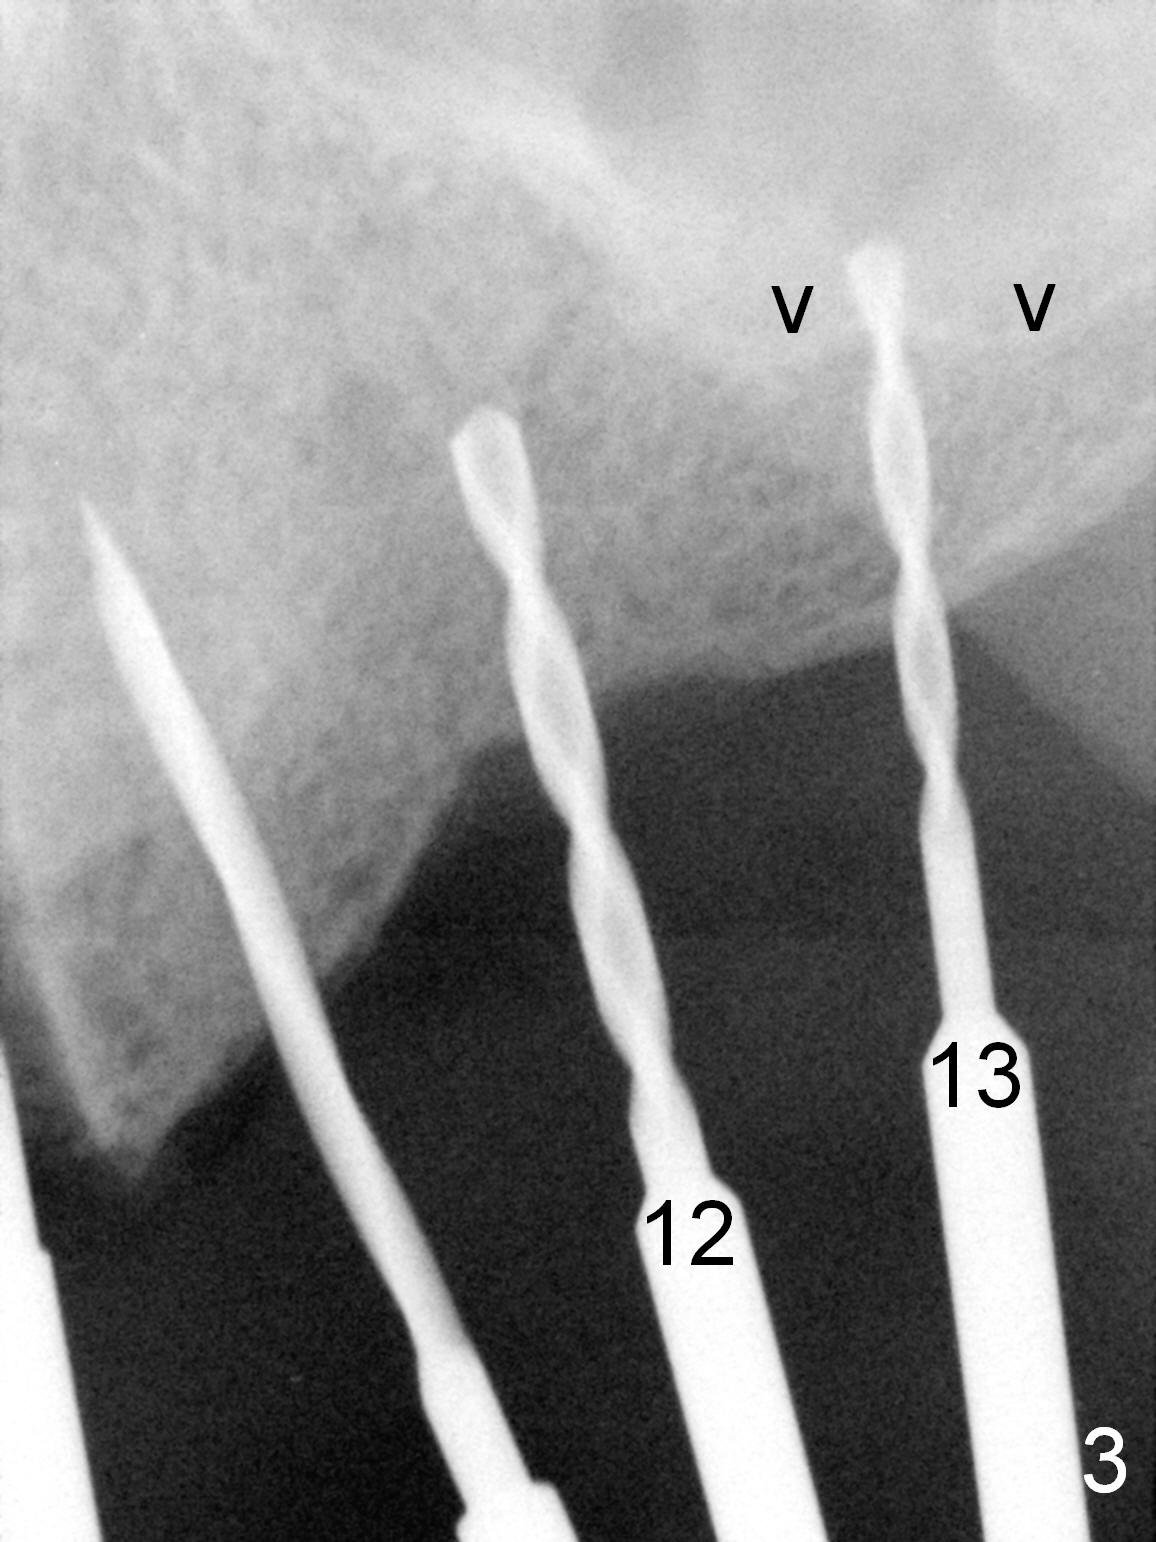

When the patient returns for implant placement (2nd visit after initial exam), he reveals that he is a dental phobic. He requests placement of 4 implants in the upper left quadrant, instead of 2. Narrow ridge is unexpected in the canine and premolar area (Fig.1). Limited bone height at #13 (Fig.3 arrowheads: sinus floor) is found when initial drills are in place (Fig.2,3). A 2-piece implant (4.5x17 mm tissue-level) is placed at #10 after extraction, while 1-piece implants are placed at 11 (3x17 mm (tissue-level, 15 °) and 12 and 13 (bone-level, 2.5x14, 12 mm, respectively; Fig.4,5). In fact the 1 piece implant at #13 is not completely placed (Fig.5). It is removed, the apical 3 threads are cut off (Fig.6 <, since a shorter implant was unavailable in the office) and the remaining implant is re-inserted. The insertion torques of the 4 implants are ~ 60, ~ 35, < 35 and 15 Ncm, respectively. After adjustment (Fig.7), immediate provisionals are fabricated at #10 and 11 (Fig.8, later splinted with composite), while perio dressing is applied around the implants at #12 and 13 and the provisionals at #10 and 11. There is no nasal hemorrhage postop. Although the perio dressing is loose 1 week postop (Fig.9), it is not removed. When the upper lip fissure (Fig.9 <) heals, provisionals at #12 and 13 are planned to be splinted to the other two ones. Two weeks postop, the upper lip fissure heals, the perio dressing dislodges and the implants at #12 and 13 are stable (Fig.10). After abutment height adjustment, a splinted provisional is fabricated over these 2.5 mm 1-piece implants (Fig.11).